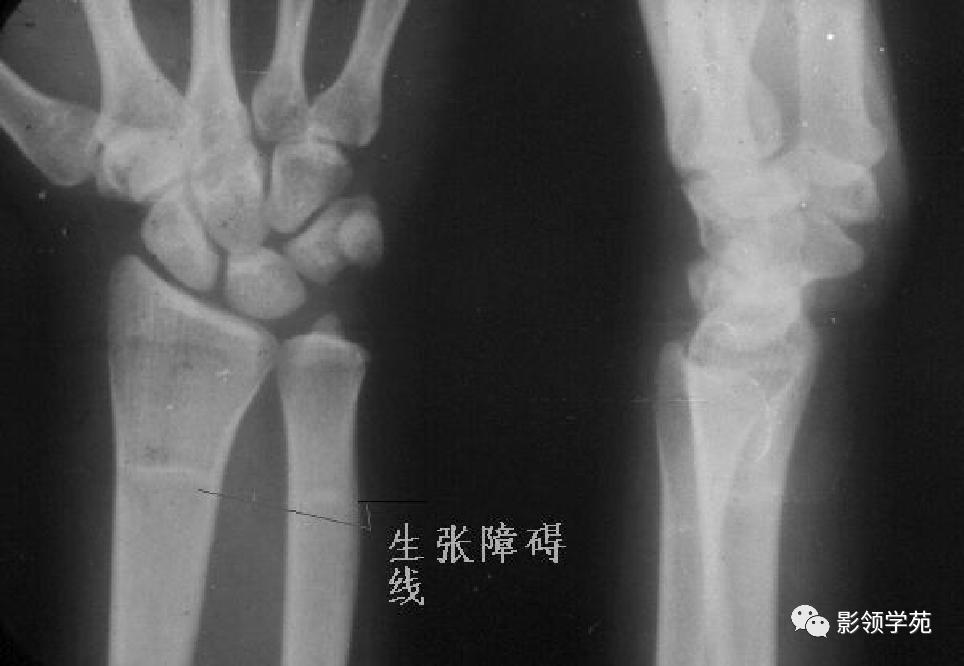

第五跖骨基底部骨折,常为横行骨折,即骨折线垂直于跖骨骨干,它是由于腓侧短肌肌腱应力所引起的撕脱骨折,也称“JONES骨折”。该骨折应与第五跖骨粗隆突起鉴别,尤其是9-15岁的儿童,常常可以出现第五跖骨基底部的骨骺,常表现为纵行透亮线,骨片边缘一般规则光滑,周围软组织无明显肿胀。

第五跖骨粗隆存在独立的骨化中心,并且可有一个或多个骨化中心,常见于10~15岁儿童。一般25岁左右与第五跖骨其余部分融合。

我们所常见的第五跖骨基底部骨折的骨折线一般都是垂直于长轴的,平行于第五跖骨长轴的骨折非常罕见。从外力方向、方式来发现,很难使第五跖骨基底部发生纵形骨折,而该处确实存在骨骺,大量的误诊就是把骨骺当骨折。